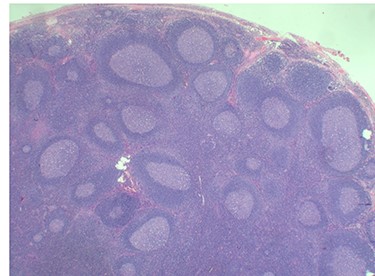

Because of the recent increase in the size of the swelling, the patient presented to our clinic and agreed to undergo excision of the swelling. A well-circumscribed swelling measuring 2.5 cm × 1.5 cm which was soft to firm in consistency was completely excised (Fig. 1). Histopathological examination showed sections of lymph node with florid follicular and germinal center hyperplasia (Fig. 2), and paracortical expansion by plasma cells, small lymphocytes and mast cells (Fig. 3). Marked eosinophilic infiltration with focal micro-abscess formation was present (Fig. 4). The features were consistent with Kimura’s disease. There was no evidence of malignancy. At 6 months follow-up, the patient had no evidence of recurrence.

Histopathology of the lymph node showing paracortical expansion by plasma cells, small lymphocytes and mast cells, and areas containing eosinophilic micro-abscesses (accumulation of inter-follicular eosinophils). Haematoxylin and Eosin stain. Magnification ×5.